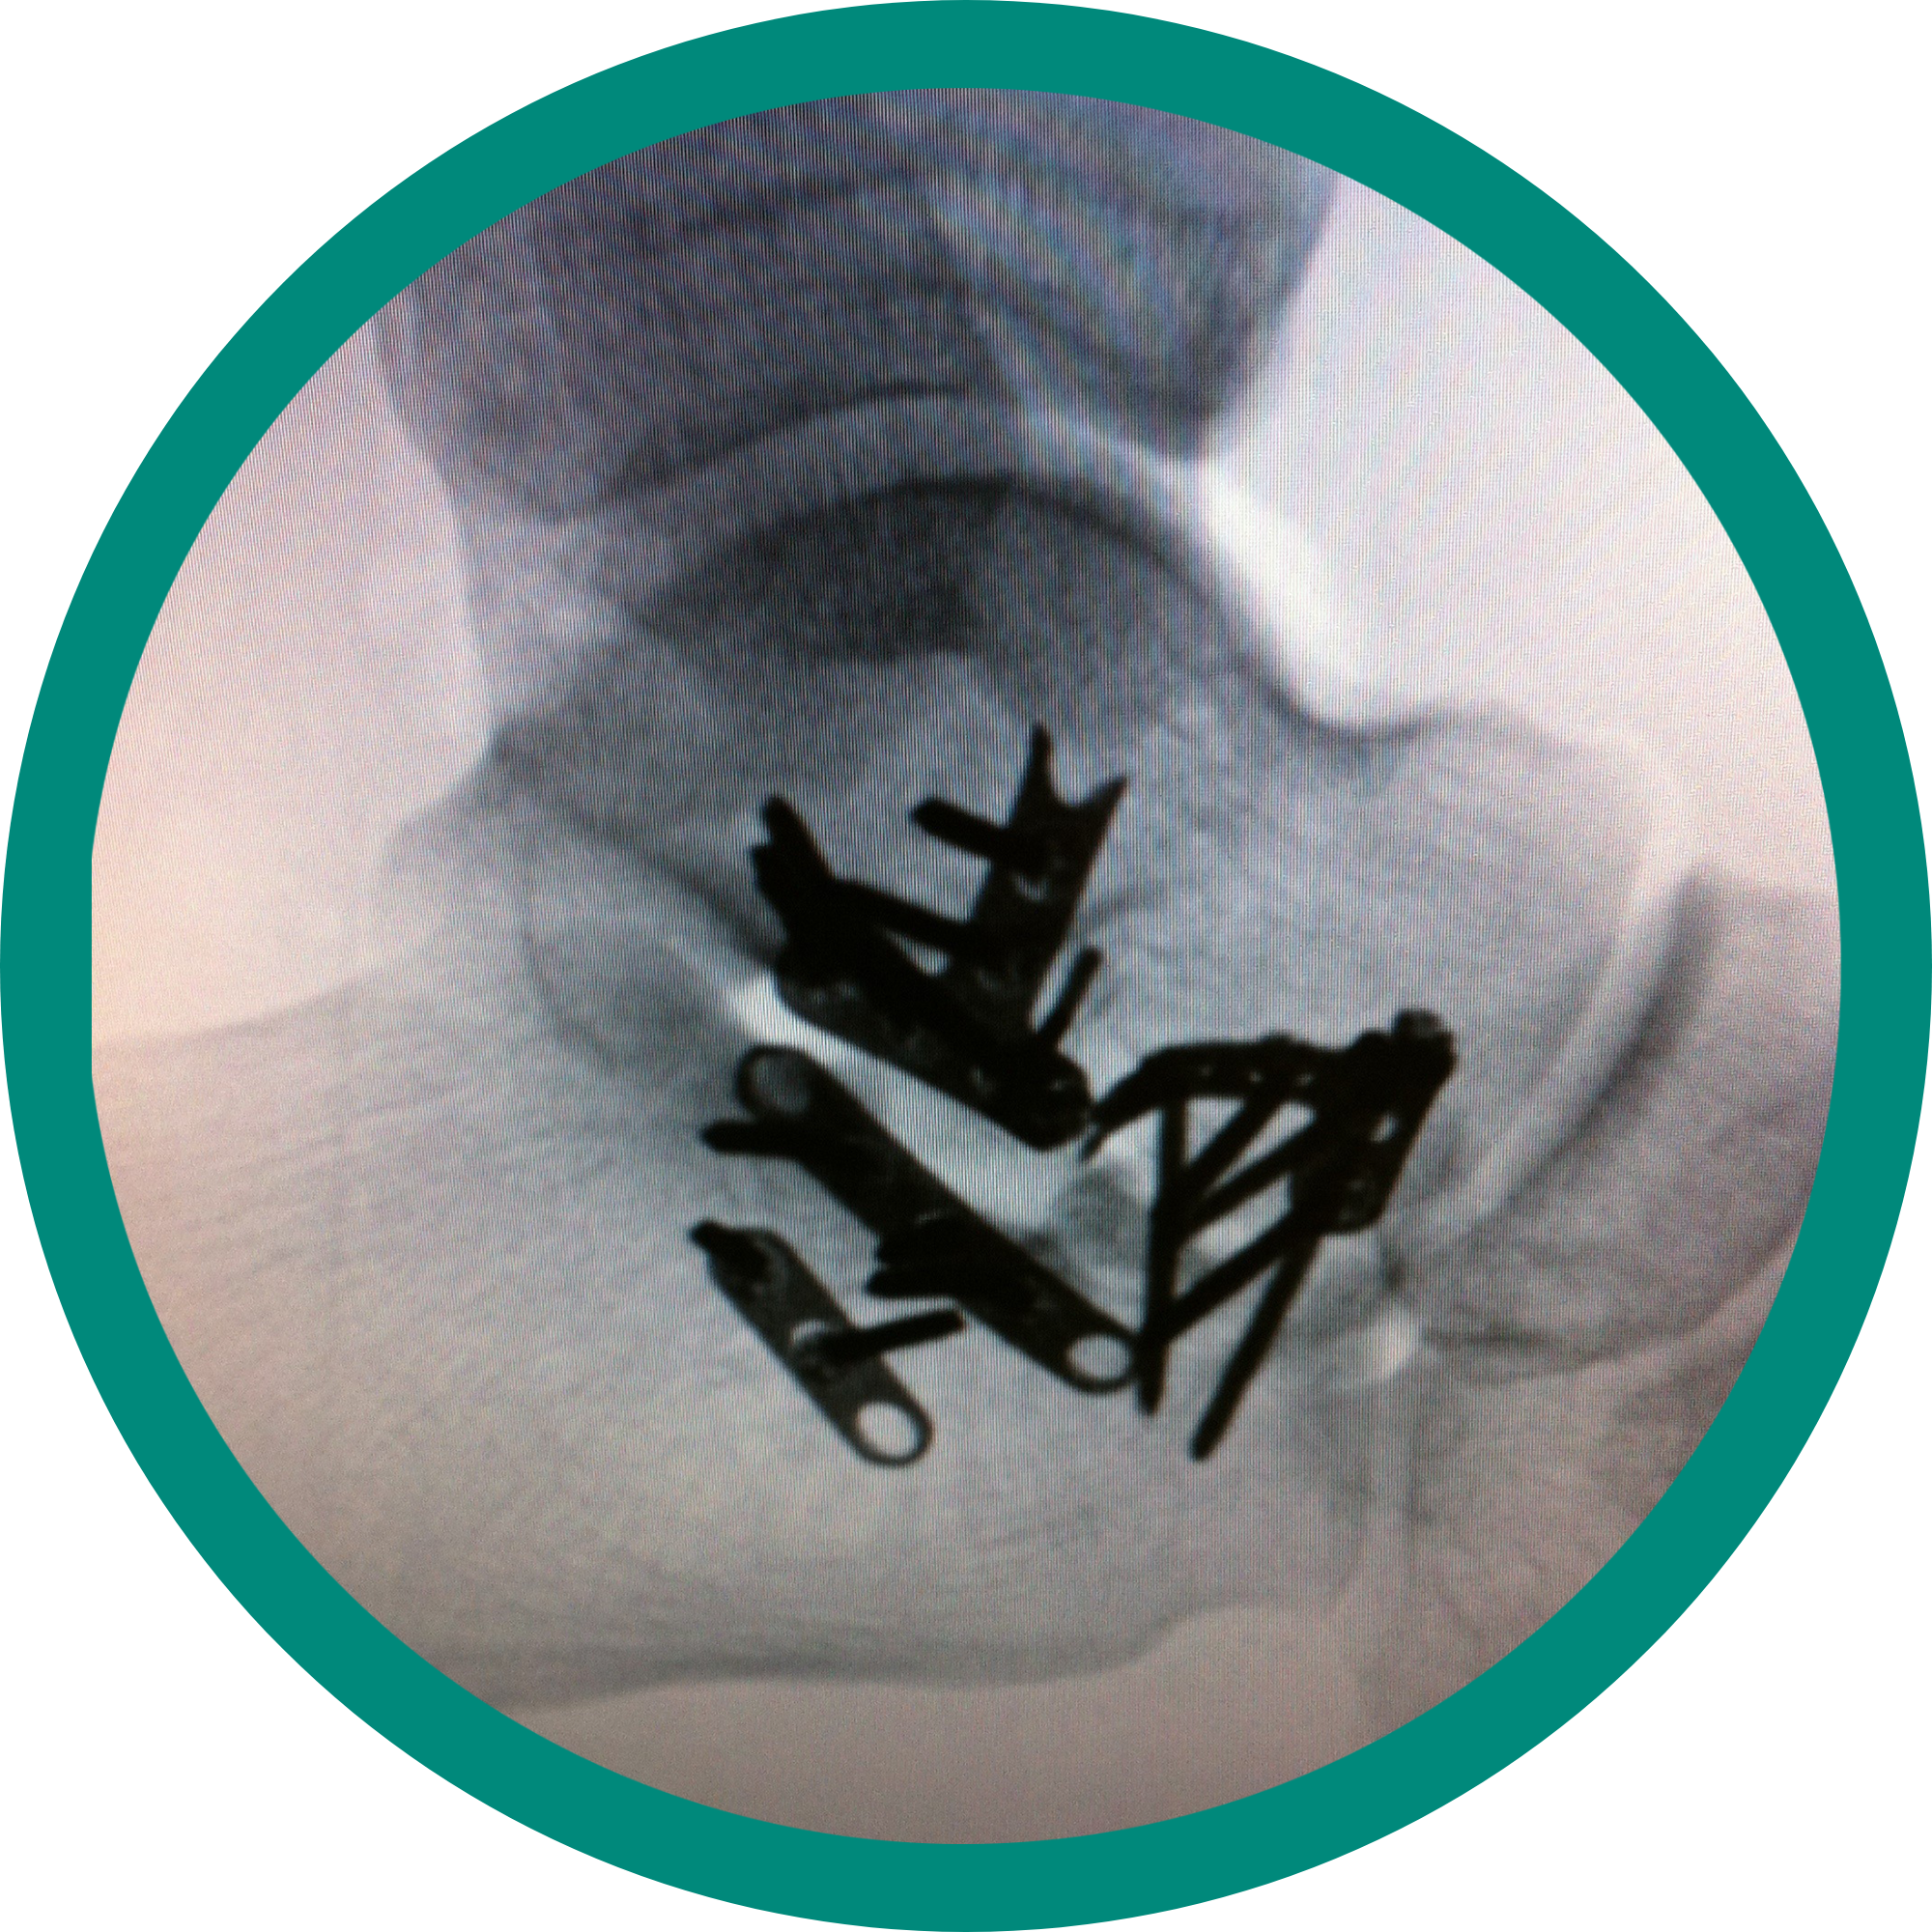

Complex trauma

Dr. Stevens’ practice is one of the few foot and ankle specialists in Illinois. He provides various care options including, but not limited to, revision surgeries, reconstruction fusions and complex trauma repairs. He also ranks in the Top 1% in patient experience nationally.

Complex reconstruction

Fractures